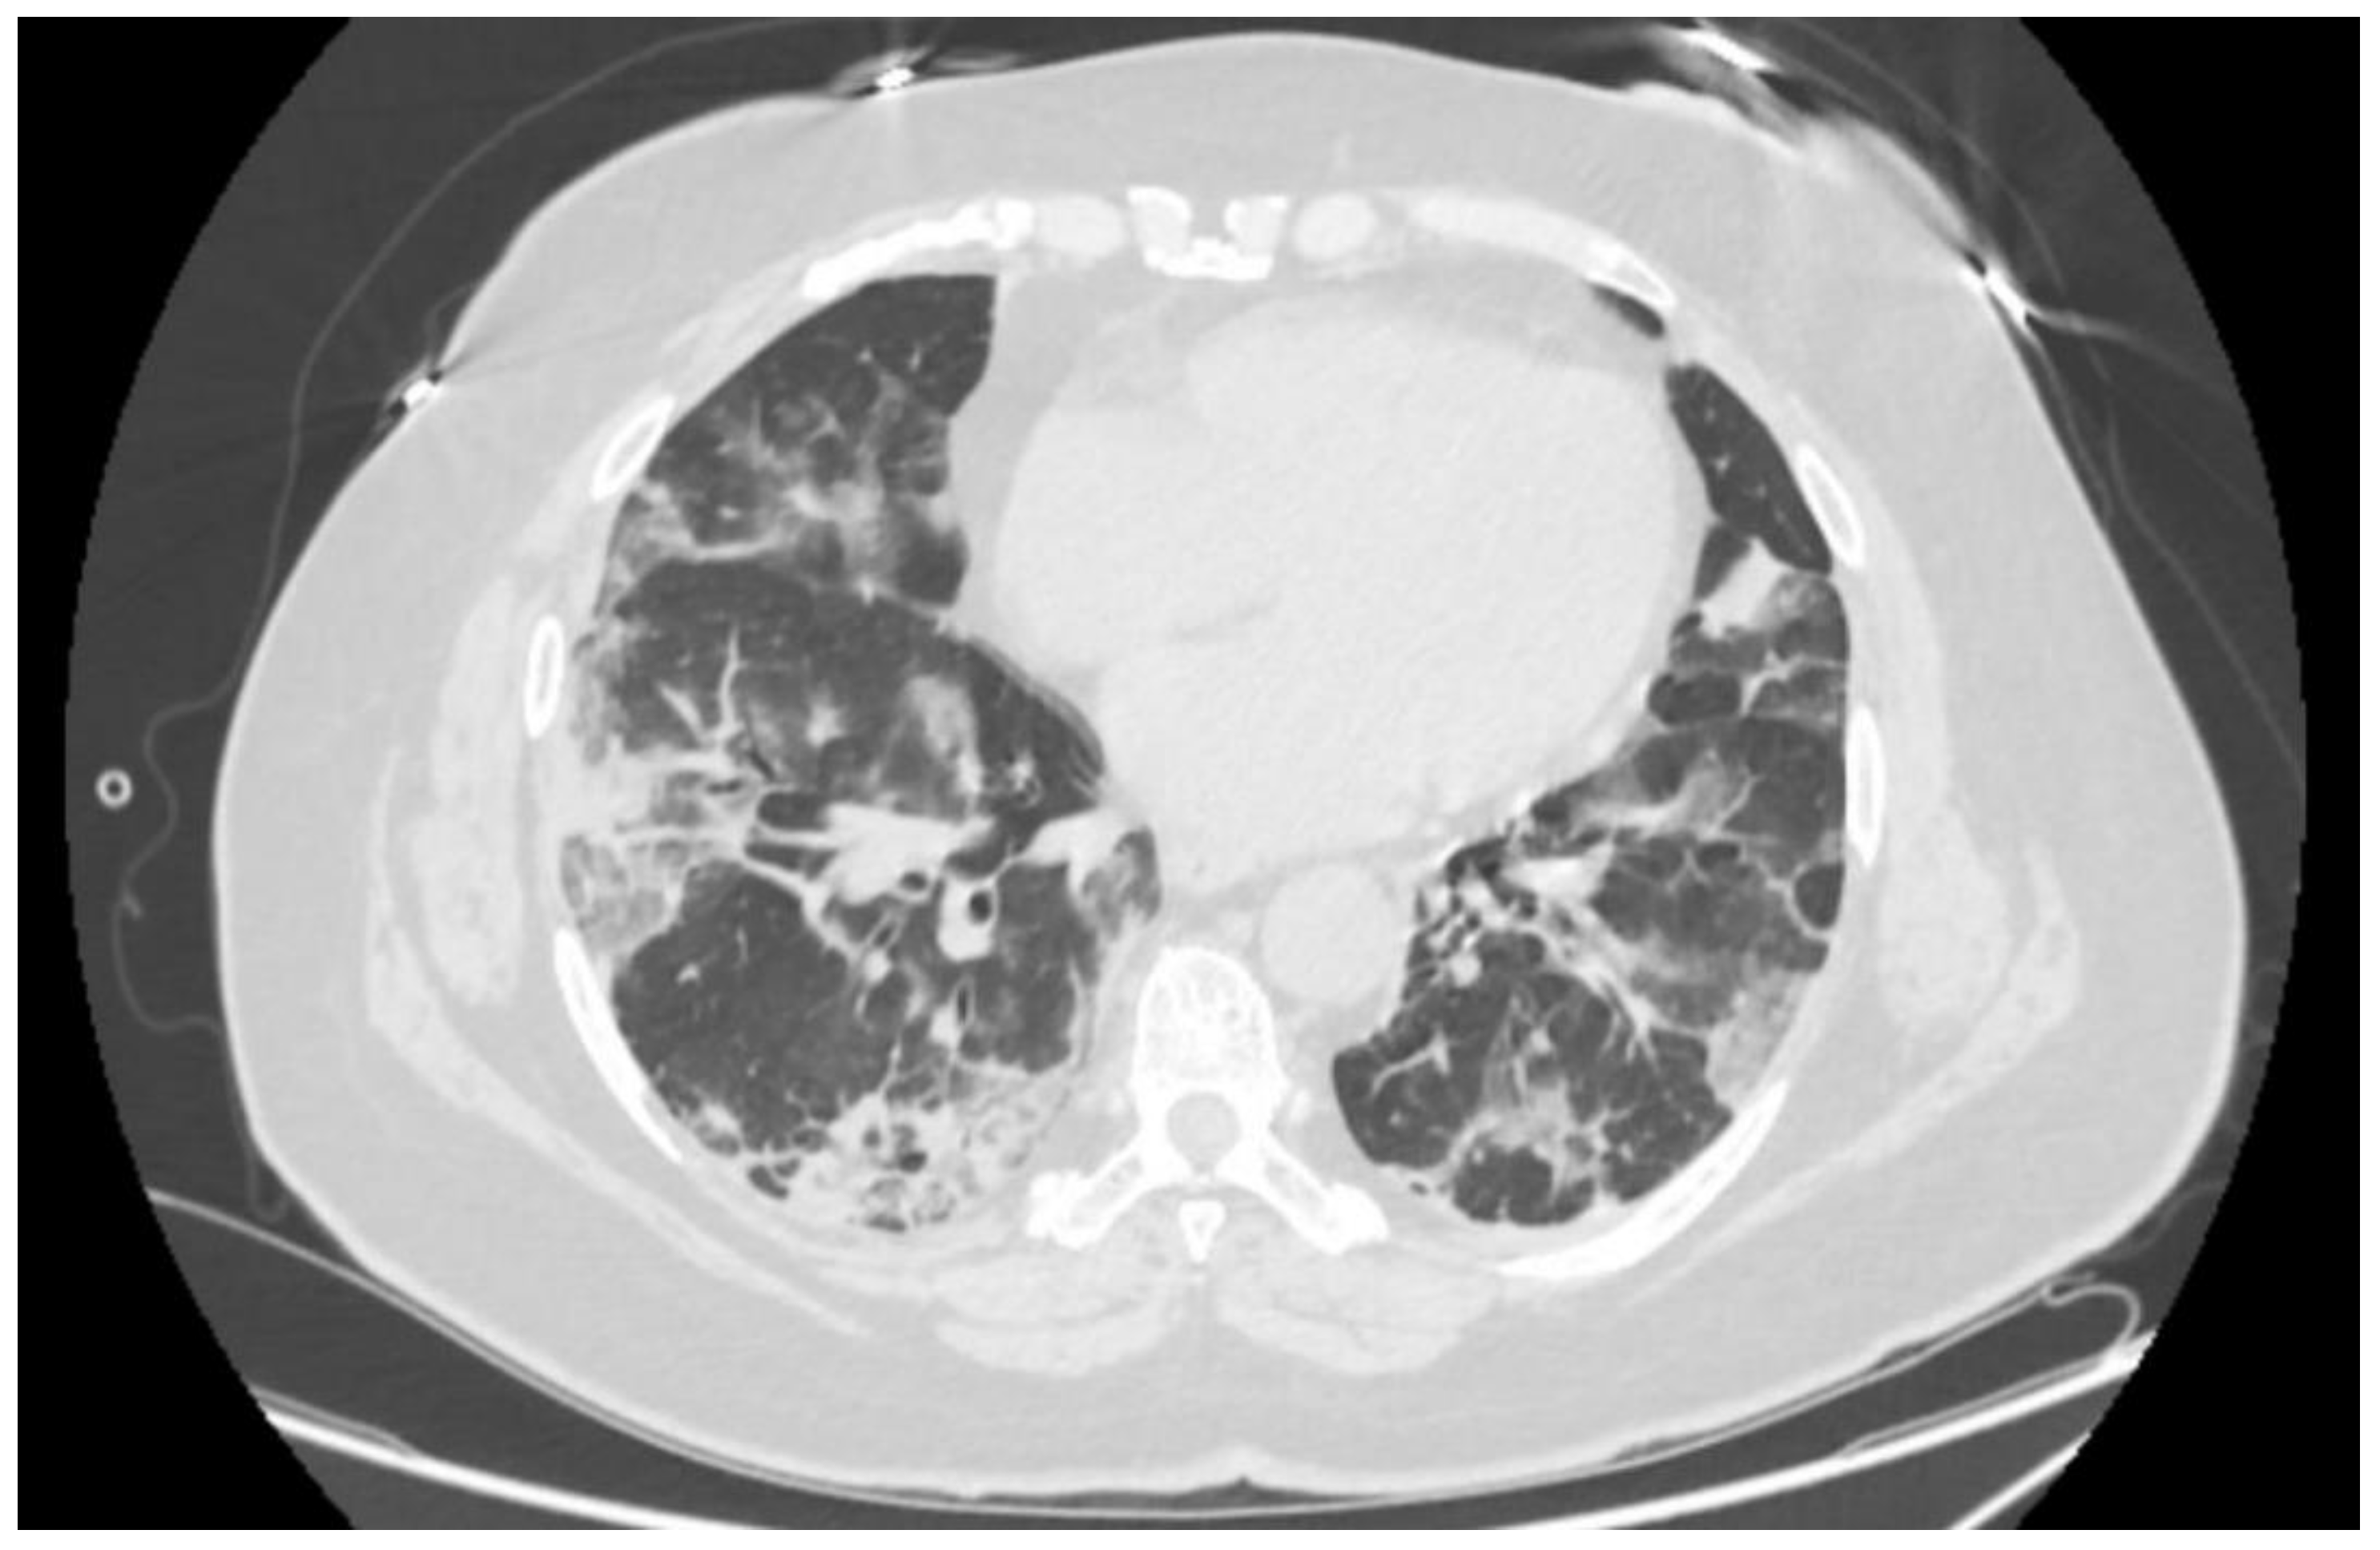

Objective findings revealed peripheral oxygen saturation (SpO2) of 80% in room air, rising to 94% with non-rebreather oxygen mask at flow rate of 12 L per minute. Her respiratory rate was 20 breaths per minute on supplemental oxygen, heart rate 78 beats per minute, and systemic blood pressure 154/78 mmHg. At this point, arterial pO2 was 68 mmHg, SaO2—96.5%. Nasopharyngeal and oropharyngeal swab was positive for SARS-CoV-2 RNA in PCR testing. Native computed tomography imaging of the thorax revealed signs of advanced bilateral atypical pneumonia in organizing stage consistent with COVID-19 pneumonia (Figure 1). The patient’s body mass index was 33.9 kg/m2.

Figure 1.

Axial computed tomography image of the lungs on the first day in the hospital.